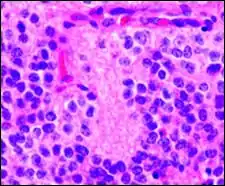

Perivascular pseudorosette

A perivascular pseudorosette consists of a spoke-wheel arrangement of cells with tapered cellular processes radiates around a wall of a centrally placed vessel. The modifier “pseudo” differentiates this pattern from the Homer Wright and Flexner-Wintersteiner rosettes, perhaps because the central structure is not actually formed by the tumor itself, but instead represents a native, non-neoplastic element. Also, some early investigators argued about the definition of a central lumen, choosing “pseudo” to indicate that the hub was not a true lumen but contained structures. Nevertheless, this pattern remains extremely diagnostically useful and the modifier unnecessarily leads to confusion. Perivascular pseudorosettes are encountered in most ependymomas regardless of grade or variant. As such, they are significantly more sensitive for the diagnosis of ependymomas than true ependymal rosettes. Unfortunately, perivascular pseudorosettes are also less specific in that they are also encountered in medulloblastomas, PNETs, central neurocytomas, and less often in glioblastomas, and a rare pediatric tumor, monomorphous pilomyxoid astrocytomas.[2]

Micrograph of perivascular pseudorosettes

Structure of a perivascular pseudorosette